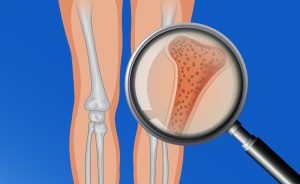

El pie es una estructura formada por varios huesos, músculos y ligamentos. Es una de las estructuras más complejas del cuerpo, y sobre donde se distribuye todo nuestro peso corporal. Nos sirve de mecanismo de acción y transmisión de fuerzas a la hora de impulsarnos cuando nos desplazamos ya sea andando o corriendo.

Existen dos tipos de pie plano, el flexible y el rígido. El pie plano valgo flexible es aquel que se produce por una alteración de la musculatura intrínseca y extrínseca del pie, así como por una laxitud muy pronunciada de los ligamentos que dan estabilidad a las numerosas articulaciones del pie. Para diferenciar si un pie plano es flexible debemos colocar a nuestro pequeño de pie en el suelo sobre una superficie estable y dura. Si al ponerle de pie, vemos como su arco plantar interno se derrumba y por lo tanto el pie se aplana por completo haciendo que el talón se desvía hacia interno, nos encontramos ante una falta de tono muscular y una posible patología. Para comprobar si es flexible, le vamos a pedir al niño que sin sujetarse en ningún lado o con una pequeña ayuda por nuestra parte, se ponga de puntillas con ambos pies. Si al realizar este gesto y al ponerse en una posición máxima, apoyando todo el peso sobre la base de los metatarsianos y los dedos el arco del pie aumenta, hablamos de que nos encontramos ante un pie plano valgo flexible. Por norma general el pie plano flexible en los niños no suele asociarse con cuadros de dolor, ni una alteración del equilibrio y de la marcha grave. Si que es verdad que podemos tener dificultad a la hora de correr o de realizar desplazamientos por superficies irregulares.